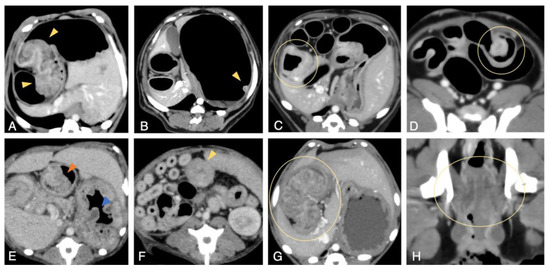

CT Scan

Diagnostic Imaging of Invasive and Metastatic Tumors